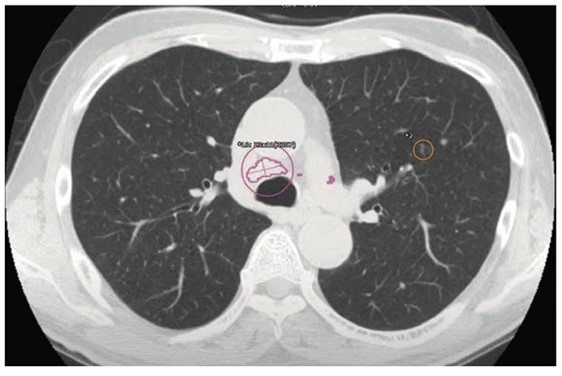

Plus.Lung.Nodule

Plus.Lung.Nodule は、胸部CT画像に対して読影を支援するための様々なROIを表示するAIです。